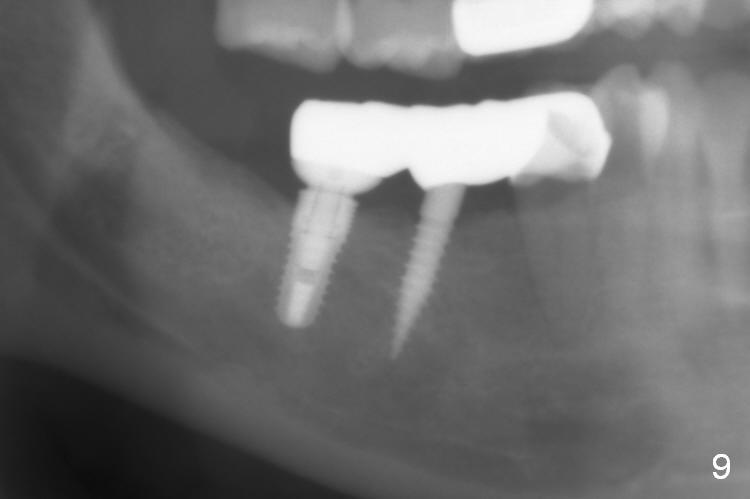

A preop photo shows different shape of pontics at #30 and 31 (Fig.1 <), suggesting different width of the edentulous ridge. Two of 8 mm parallel pins are inserted for position and trajectory (Fig.2 (red dashed line: the superior border of the Inferior Alveolar Canal). When they are removed from the osteotomy sites, the narrow ridge at #30 is shown (Fig.3). A 3x12 mm 1-piece implant is placed at #30, while a 4.5x10 mm 2-piece one at #31 (Fig.4,5). It appears that it is necessary to place an implant at #32, since the tooth #1 is present (Fig.5). The suggestion is rejected by the patient due to finance. After extraction of the tooth #32 and insertion of collagen plug, an immediate splinted provisional is fabricated to cover the #32 socket as well (Fig.6). The provisional is modified (to remove the portion that covers #32 socket) 3-4 weeks postop.

The patient returns for final restoration 3 months postop; bone resorption around the 1-piece implant is minimal (Fig.7). The definitive restoration is also splinted. The latter is further justified when the implant at #30 is found to be distal prior to cementation (Fig.8 *). It appears that implant spacing at the root level is more critical than parallelism, as compared to Fig.7. Let us improve this aspect. Bone loss around the implants remains minimal 7 months post cementation (Fig.9). It is the same 1 year 8 months post cementation (Fig.10), as compared to a cantilever FPD on the other side (Fig.11). The bone density around the implants at #30 and 31 increases 2 year 8 months post cementation (Fig.12).